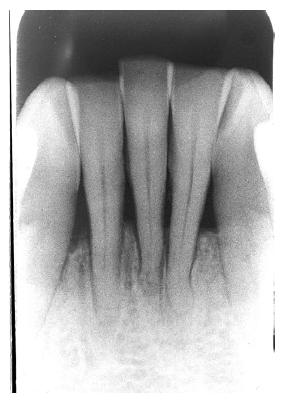

Figure 13 illustrates apical periodontal pathosis in the area of the right central incisor. Note the loss of continuity of the lamina dura and the widened periodontal ligament space on the affected side.

Figure 13 - Apical Periodontal Pathosis

Figure 13